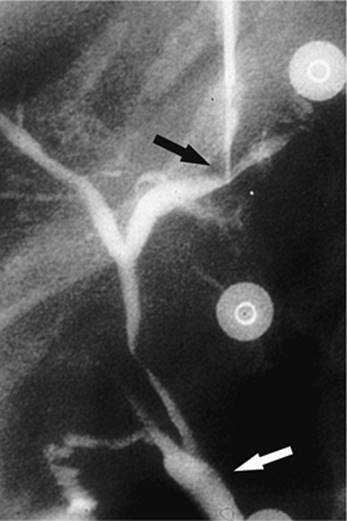

000431

Figure 35.14. Failed endoscopic placement of common bile duct (CBD) stent due to the presence of a large mass (black arrow) within the CBD. (Image courtesy of James Caridi, MD.)

000434

Figure 35.15. Successful percutaneous drainage using a left-sided biliary duct. Note that the drainage catheter has been advanced past the obstruction and into the small intestine. (Image courtesy of James Caridi, MD.)